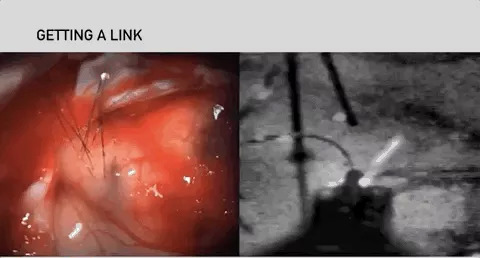

近日,埃隆·马斯克展示了旗下脑机接口公司Neuralink的最新技术。简单来说就是将硬币大小的芯片用手术机器人V2和可运作设备Link V0.9植入颅顶的大脑皮层部分,让机器能够获取大脑内部的电极信号,从而传输至外部设备之上,实时完成脑机之间的数据传输。

不能否认马斯克确实具备Steve提到的这些能力。早在去年,Neuralink就曾在旧金山召开过发布会,会上马斯克表示要用脑机接口实现让瘫痪患者操控计算机的目标。Neuralink的总裁Max Hodak表示,研究人员会在脑颅上使用无痛激光钻孔的方法植入侵入式芯片,尽可能减少侵入式手术对大脑的损伤,预计在2020年开始临床试验。